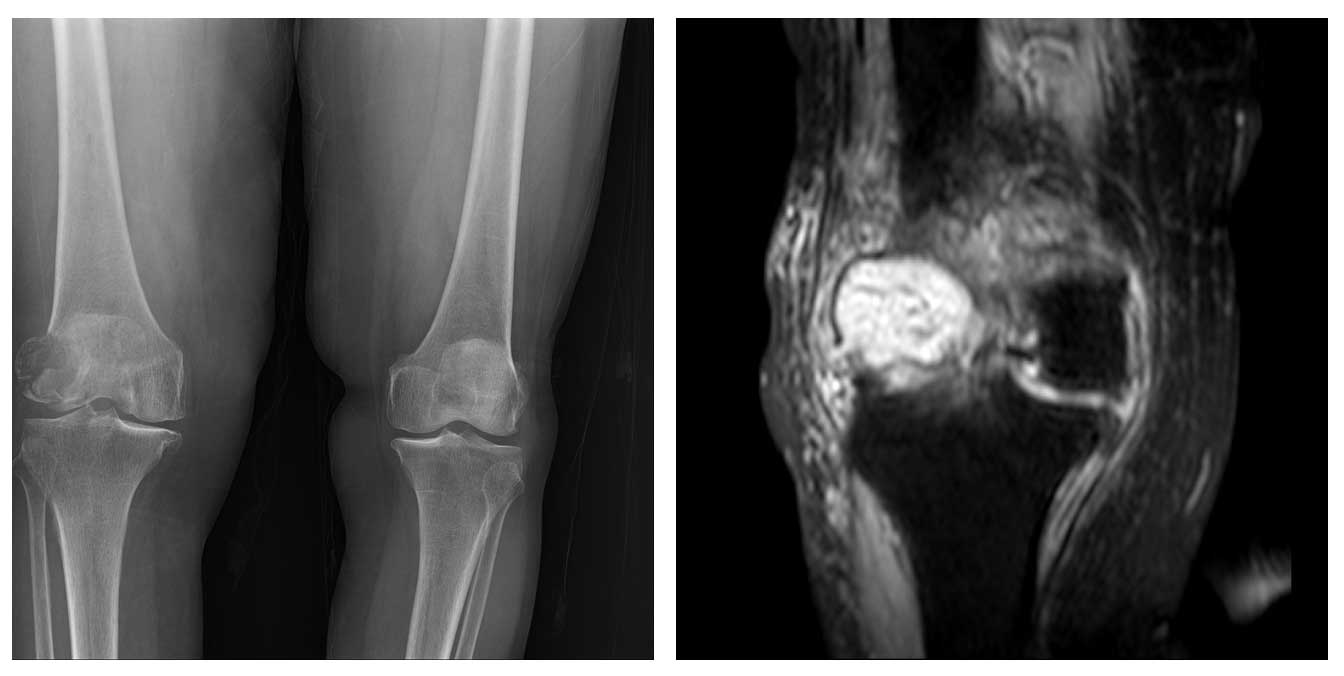

Ameliyat Öncesi: Röntgende sağ distal femur lateralde litik lezyon ve kırık, MR’da tümör dokusu ve yaygın ödem görülmekte.